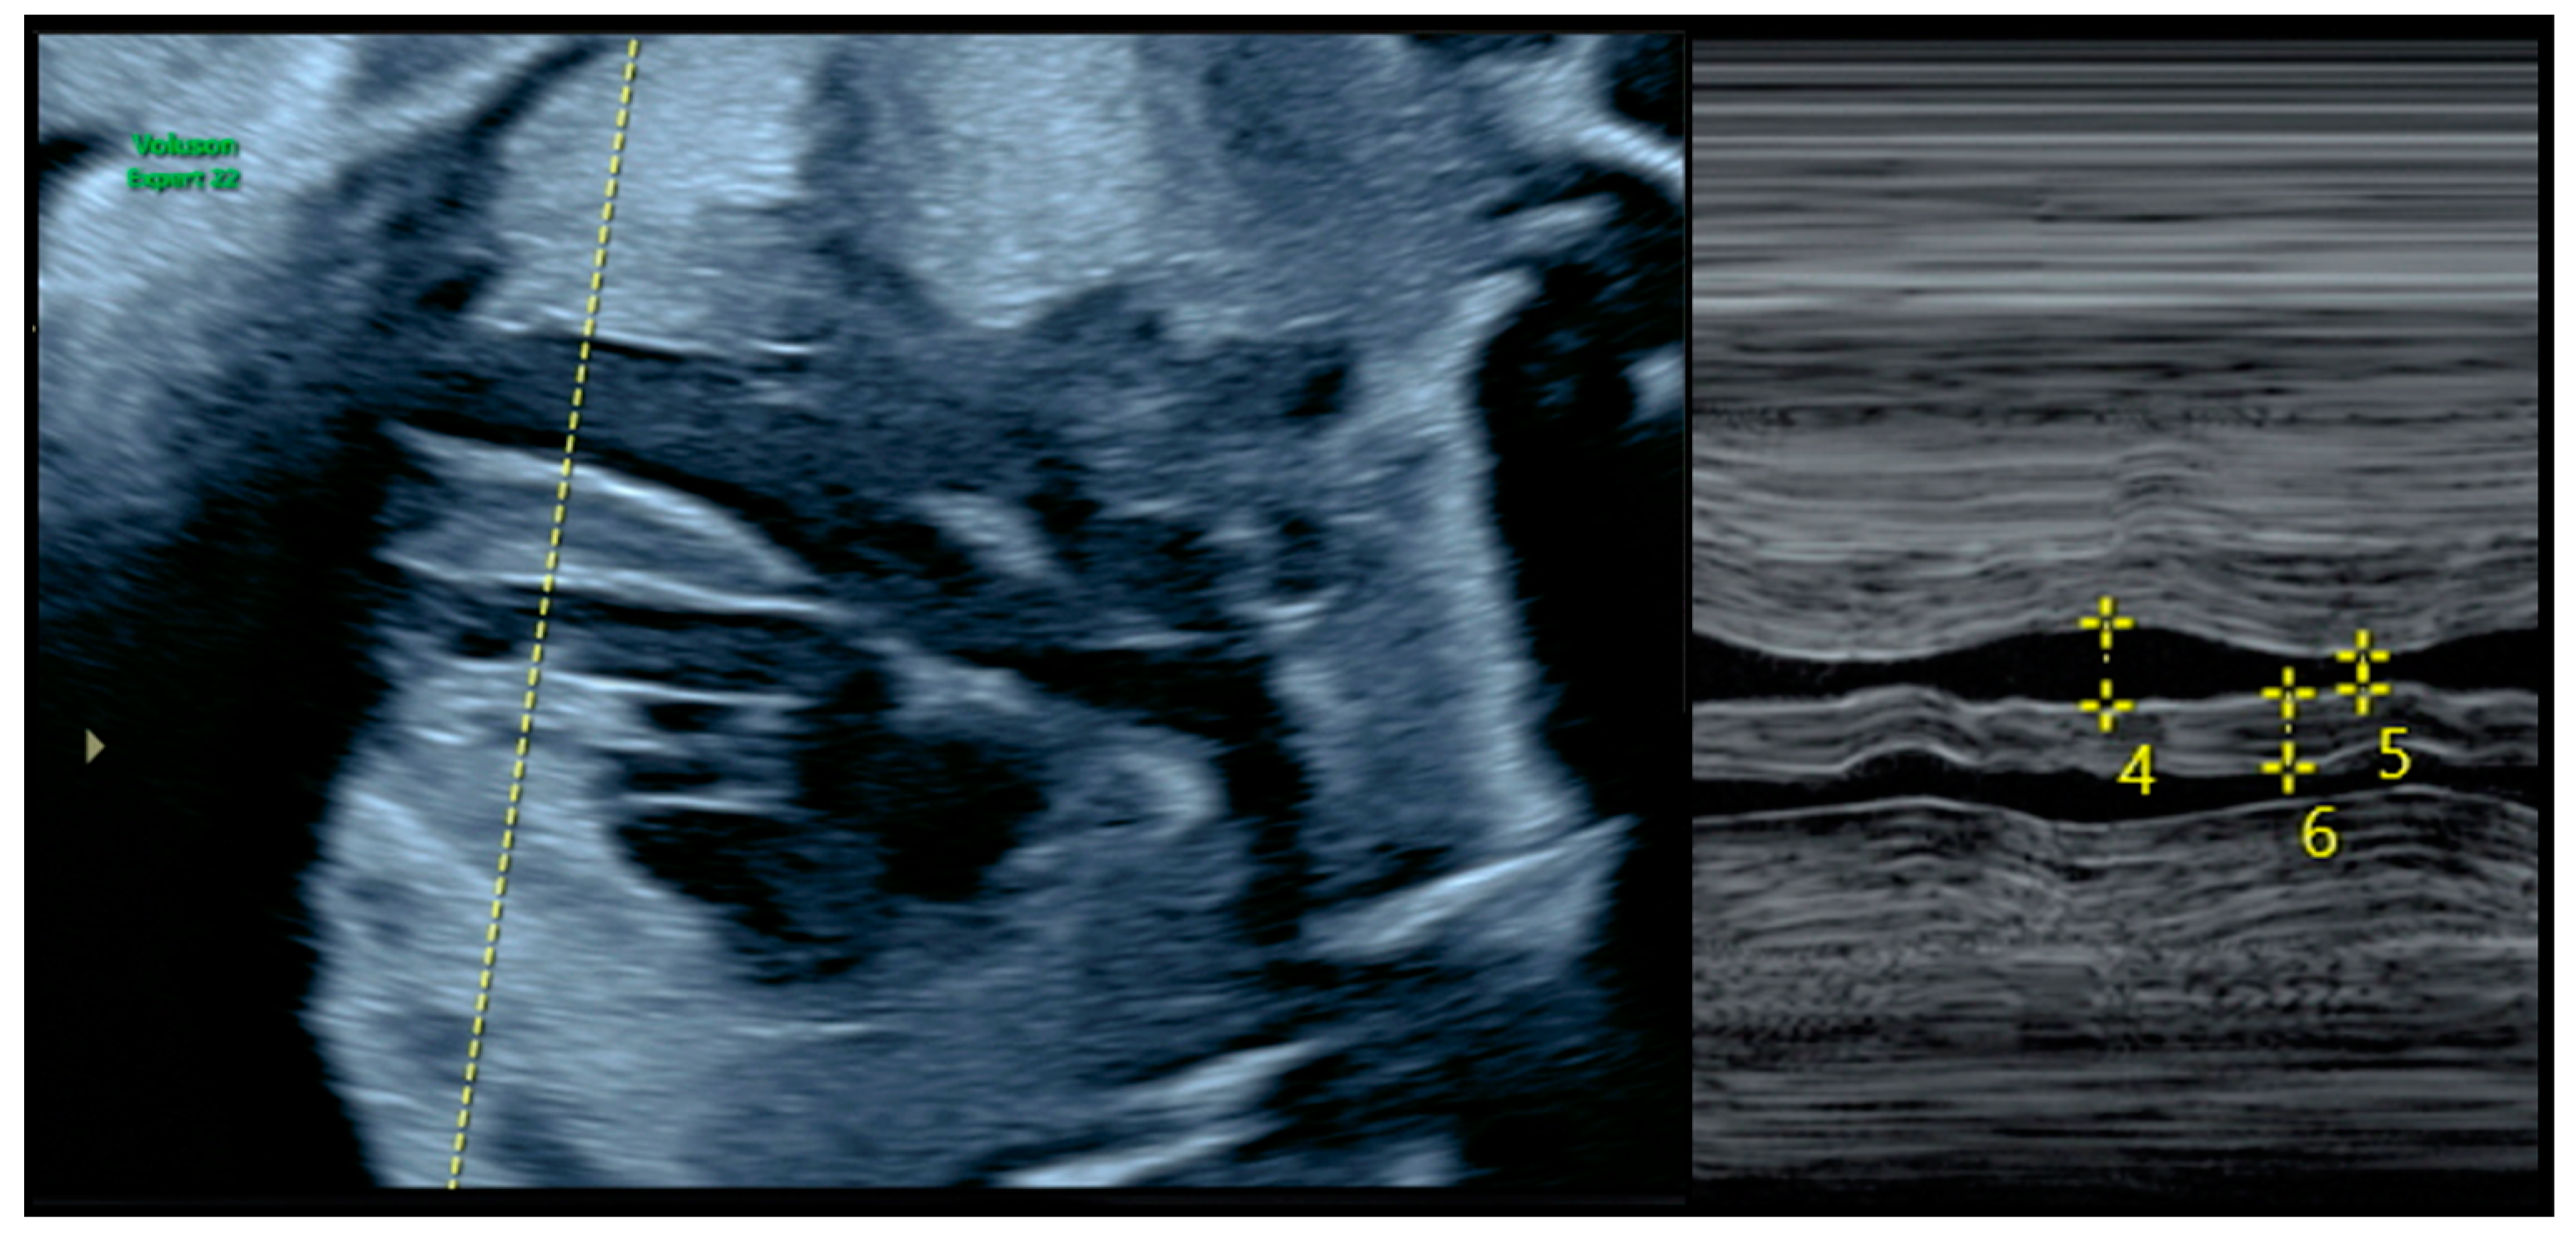

2.2. Diagnosis of FHCM and Echocardiographic Parameters